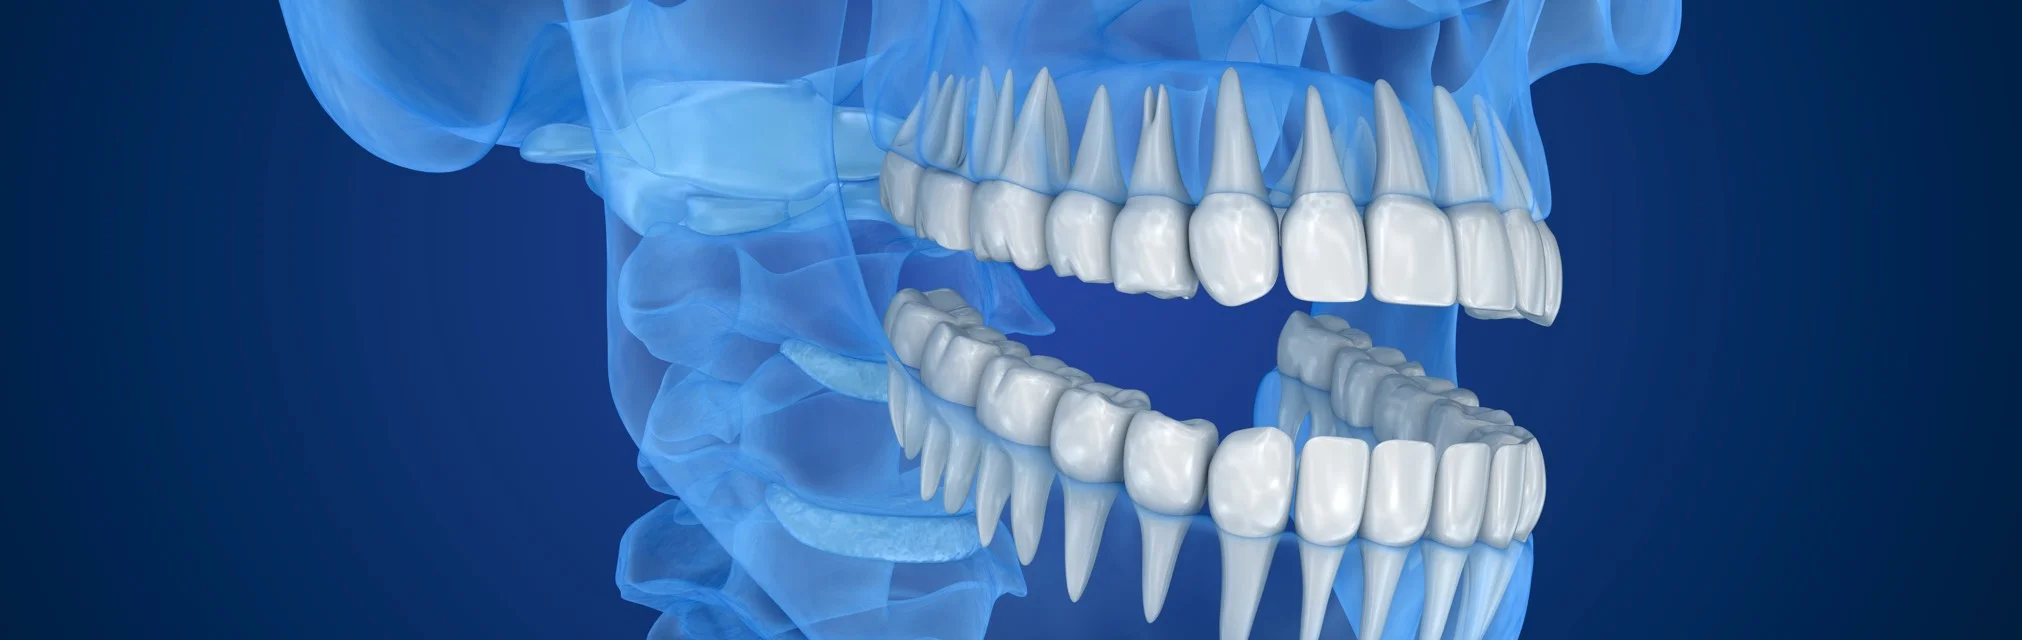

3D снимки позволяют стоматологам рассмотреть зубы под разными углами.

Врач изучает 3D снимки на компьютере и в отличии от 2D снимков, он может крутить изображение под любым углом, который ему необходим, заглядывать «внутрь» каждого зуба.

Сравнение подходов в изучении 3D снимков